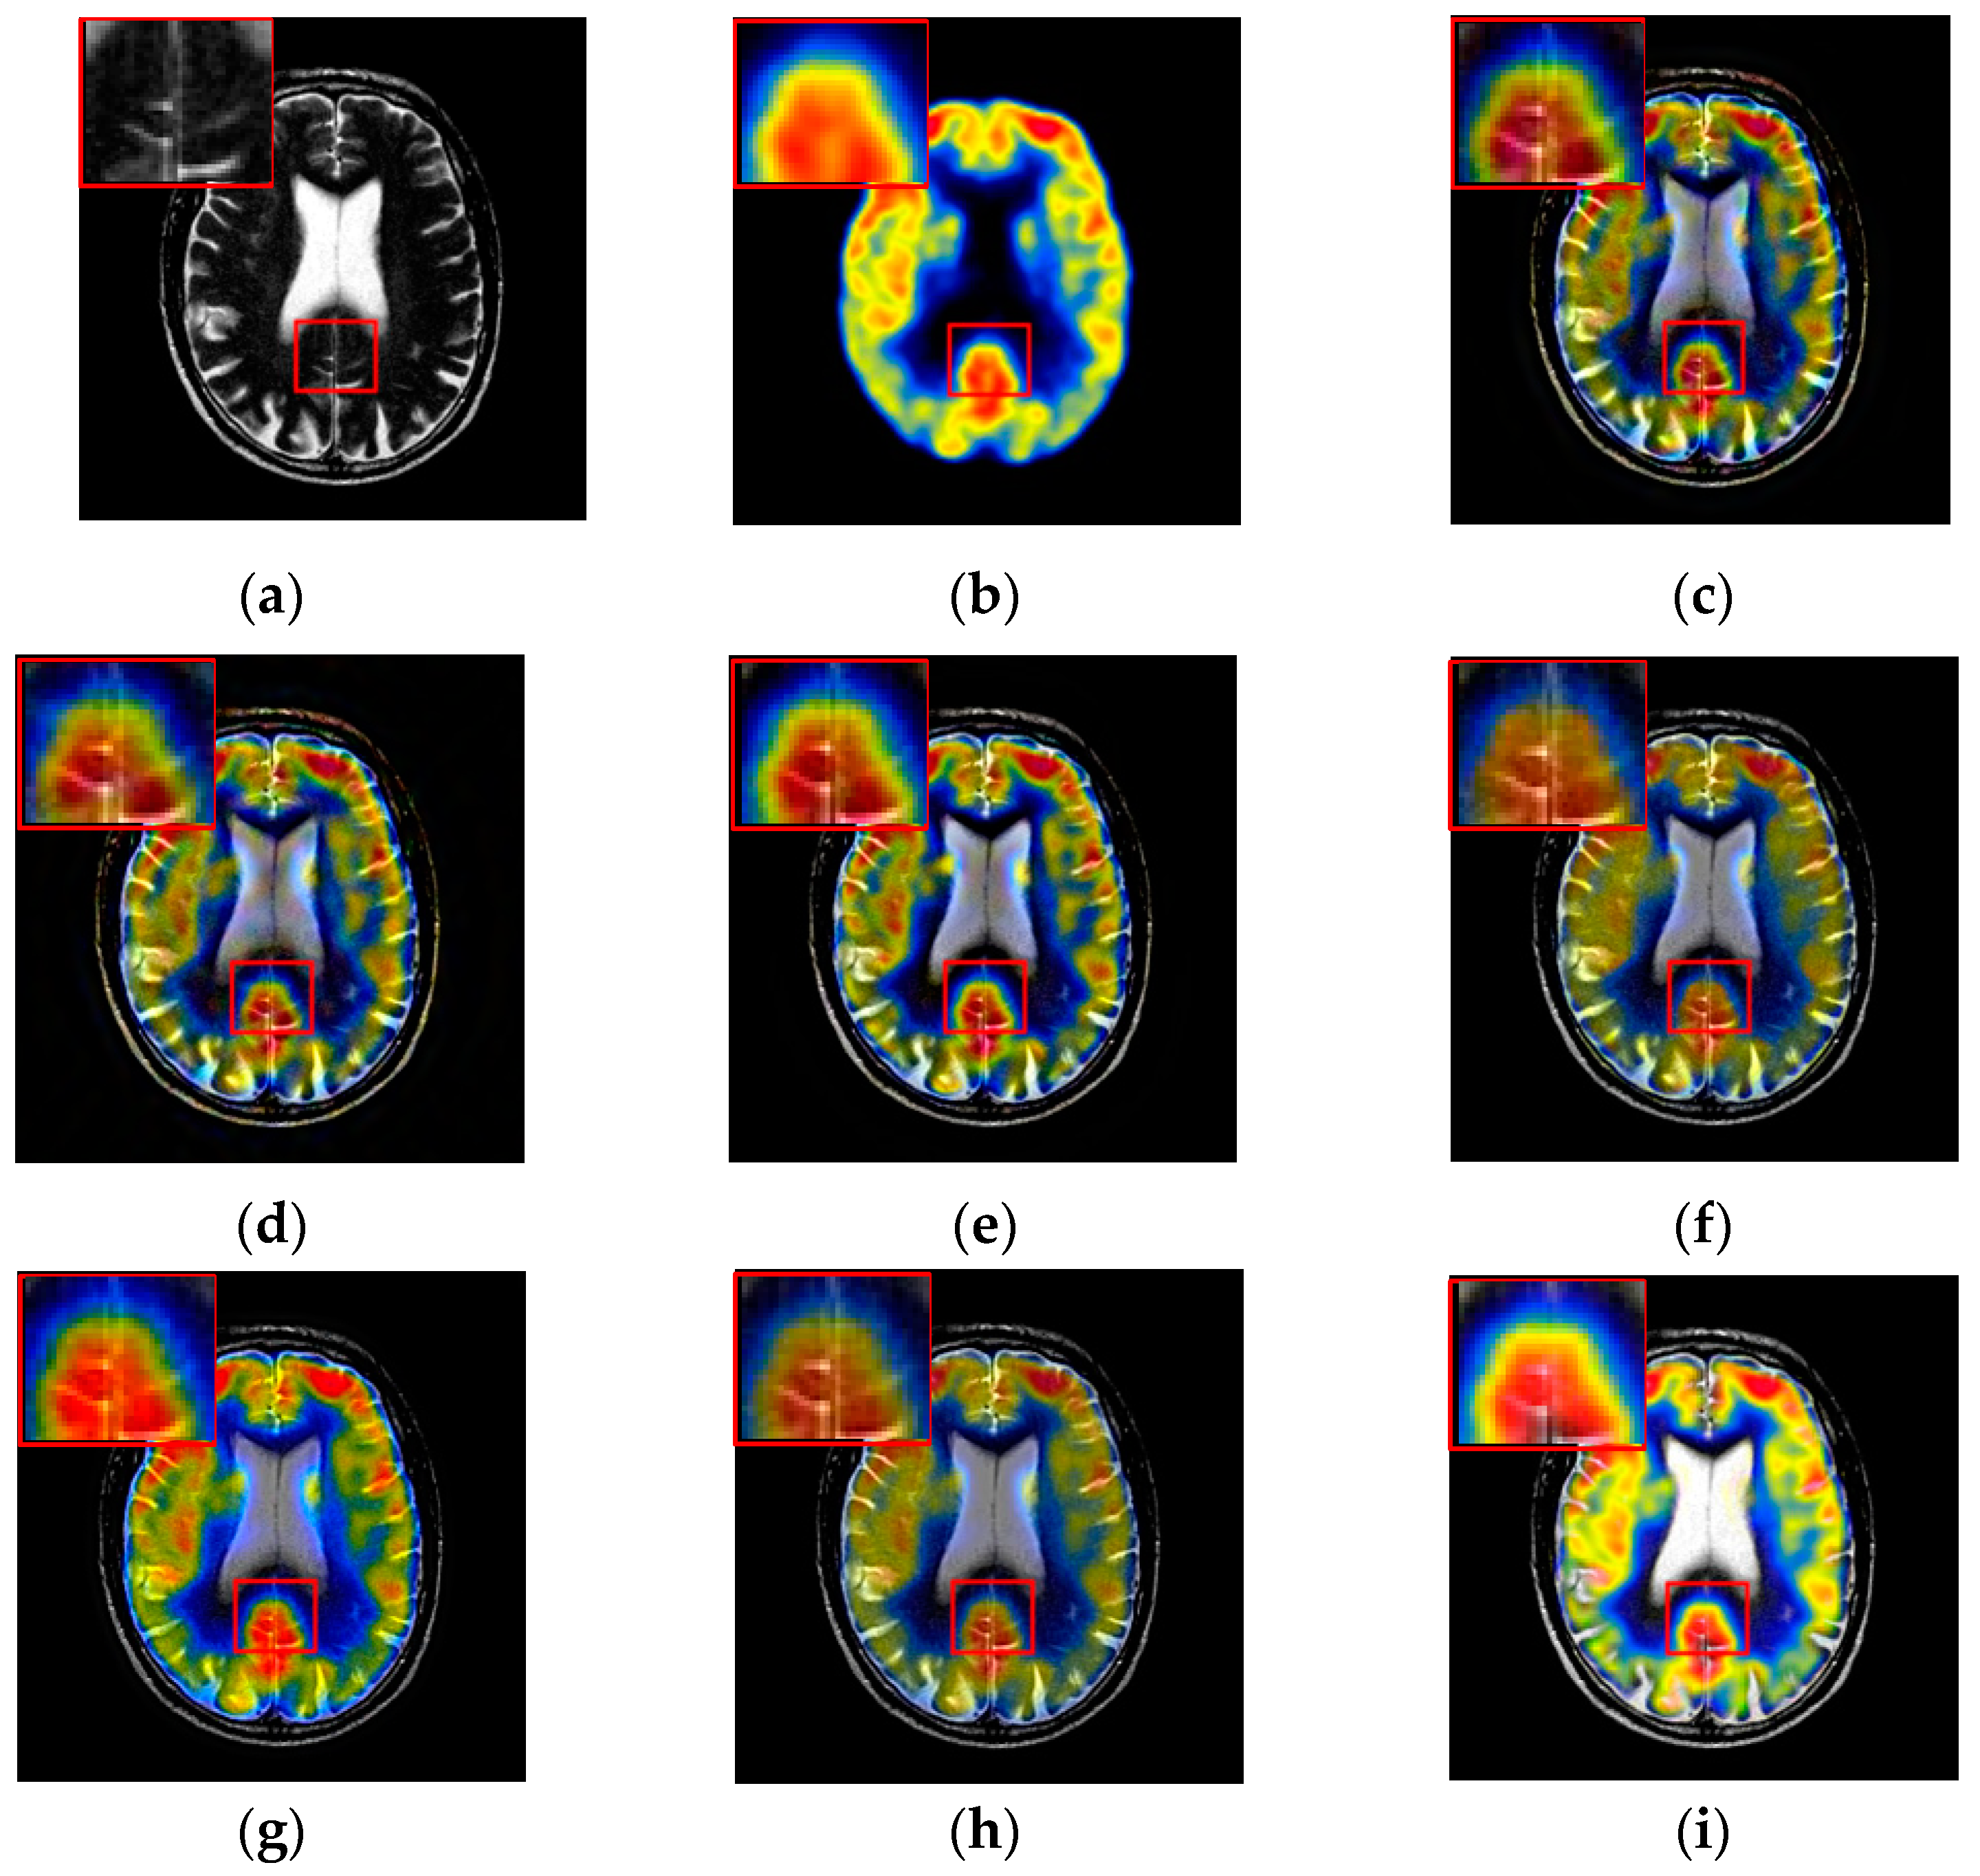

3.3. Fusion Results by Subjective Visual Effects Analysis

The results of the first set of experiments are shown in Figure 7, and the source MRI and CT images are listed in Figure 7a,b. The fused images obtained by the DCTWT, Curvelet, NSCT, Liu-ASR, Kim, Zhu, and the proposed method are displayed in Figure 7c–i, respectively. To facilitate subjective visual comparisons, local regions enclosed by red colored rectangular boxes in Figure 7 are enlarged and presented in the bottom right corners of their respective images. We can notice that the diverse fusion performance generated by different methods in retaining the brightness information and edge detail the information of source medical images. Despite the MST methods expressing source information with different scales and directions, all of the results obtained by DTCWT, Curvelet and NSCT in Figure 7c–e still produce some distortion, which heavily decreases the qualities of the medical images. Meanwhile, after careful observation, we can find the fusion results generated by Liu, Kim and Zhu can preserve details well from MRI. However, the brightness active level is relatively lower than the source CT image, which indicates the loss of useful information. It can be seen from Figure 7i that the fusion result obtained by the proposed method has the best performance in terms of retaining brightness information and detail information, which indicates that the visual effect of the method is the best.

Figure 7.

Fused results of MRI/CT medical images by different methods. (a) MRI; (b) CT; (c) DCTWT; (d) Curvelet; (e) NSCT; (f) Liu-ASR; (g) Kim; (h) Zhu; (i) Proposed.

The fusion results of different methods about “MR-T1/MR-T2” (see Figure 8a,b) are shown in Figure 8c–i. For this experiment, the detail information (shape, edge, texture et. al) in the red rectangle is mainly from the MR-T1 image while the energy information (brightness, contrast et.al) mainly from MR-T2 image. Among these fusion results, it can be seen that the details of the fusion results produced by the DTCWT, Curvelet and NSCT methods are severely damaged, especially the Curvelet method. Although the Liu-ASR, Kim and Zhu methods can relatively effectively protect the edge details of the source image, they do not protect the contrast of the image well. This is very disadvantageous for medical images with high-quality requirements, and is not conducive to subsequent medical image processing and recognition tasks.

Figure 8.

Fused results of MR-T1/MR-T2 medical images by different methods. (a) MR-T1; (b) MR-T2; (c) DCTWT; (d) Curvelet; (e) NSCT; (f) Liu-ASR; (g) Kim; (h) Zhu; (i) Proposed.

By comparison, our fusion result (Figure 8i) can not only effectively protect the edge detail information of the source image, but also maintain the contrast of the source image, which is mainly due to the detail enhancement processing of training set and the clustering techniques to classify brightness and detail groups before dictionary learning. At the same time, little artificial false information is introduced in our fusion result, which means that the visual effect of the proposed method outperforms others methods in this experiment.